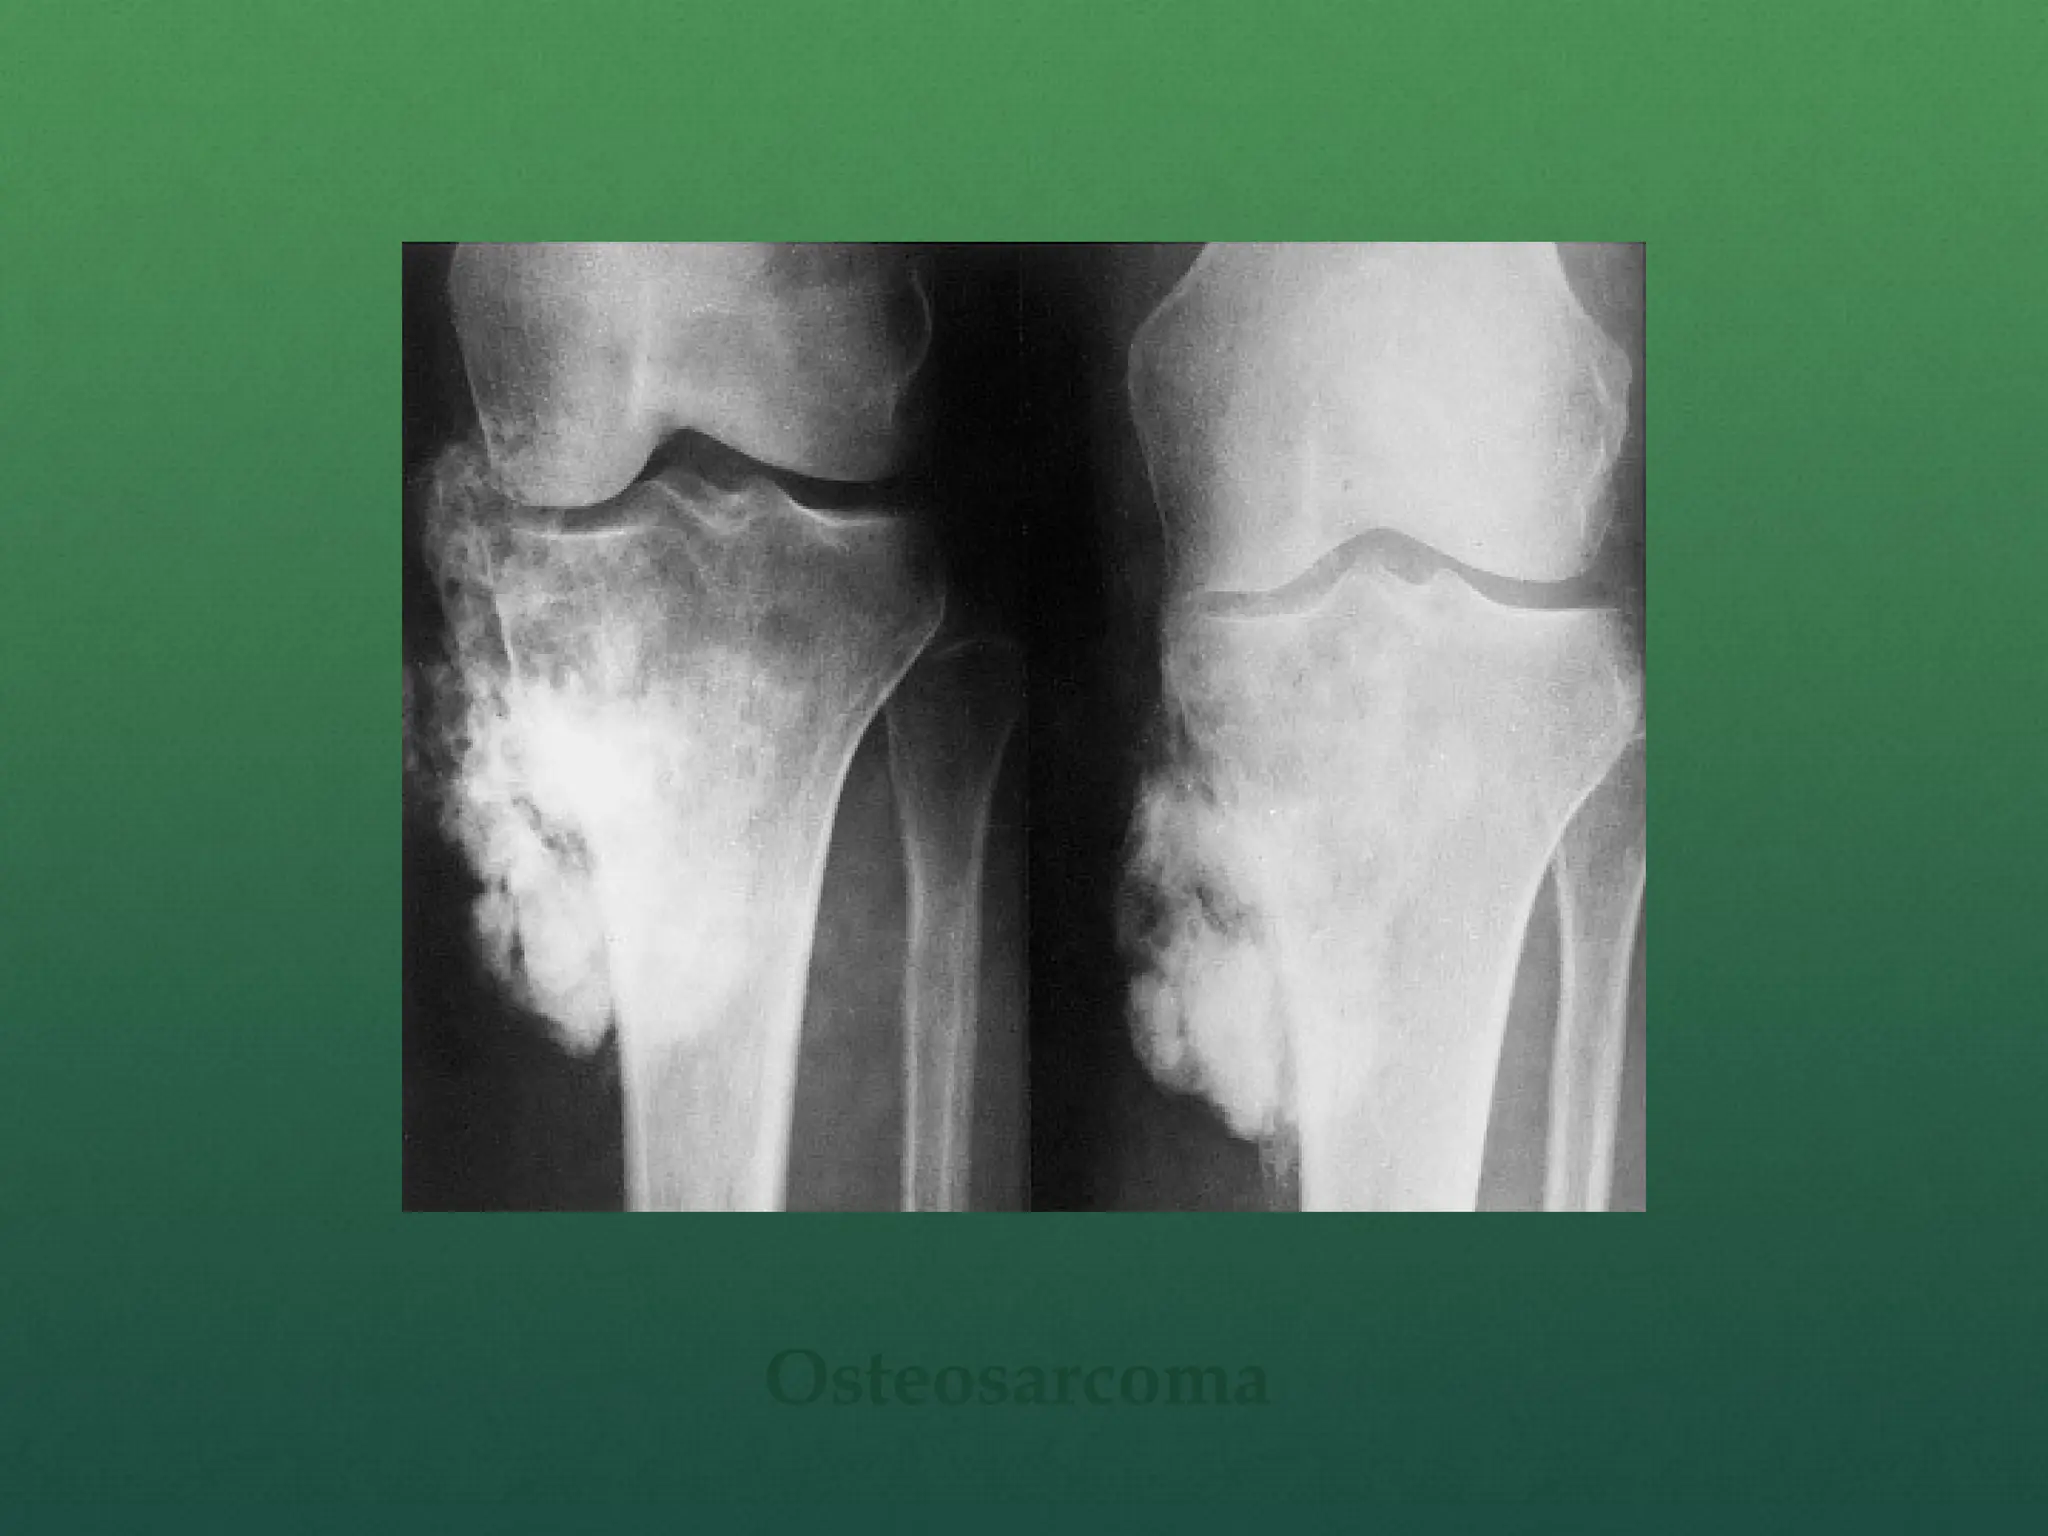

 Classic X-ray findings:

1. Codman's triangle (periosteal elevation)

2. Sunburst pattern/Sunrays appearance

3. Bone destruction

4. Ill-defined margins

Osteosarcoma